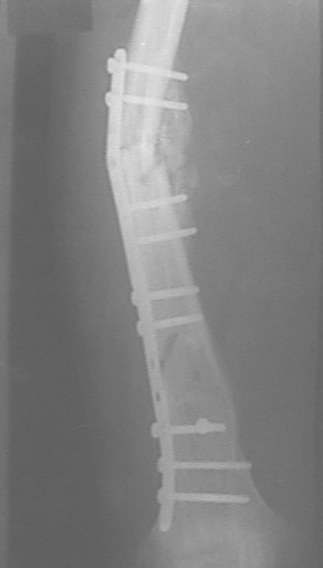

Интересно, какие соображения легли в основу выбора? Вроде LCP и сильно недешевы, и демонстрируют свои замечательные свойства в большей мере при околосуставных проблемах?

У нас, наверно, была бы сделана чрескожная остеотомия малоберцовой кости, формирование и рассверливание канала большеберцовой, закрытая остеоклазия, и закрытое же штифтование. За счет устранения варуса дефицит длины уменьшится. Можно и подтянуть дистрактором одномоментно.

При невозможности или чрезмерной травматичности одномоментного восстановления длины можно пойти двухэтапно (аппарат, потом гвоздь). Похожий пример см. тут. Прошло уже года полтора после остеосинтеза. Может, коллега Зырянов покажет годичный результат, если есть?

Александр Николаевич, к сожалению больной не является на контрольные осмотры. Я последний раз видел больного, когда прошло 7 месяцев после операции БОС. У него все хорошо. Каких либо жалоб и ограничений в нагрузке нет. Высылаю снимки до операции и последние снимки.